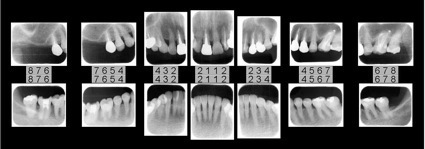

お口の中を14箇所に細かく分けてレントゲンを撮影します。レントゲンでは目視や写真では確認できない歯の中の状態と骨の状態も調べることができます。